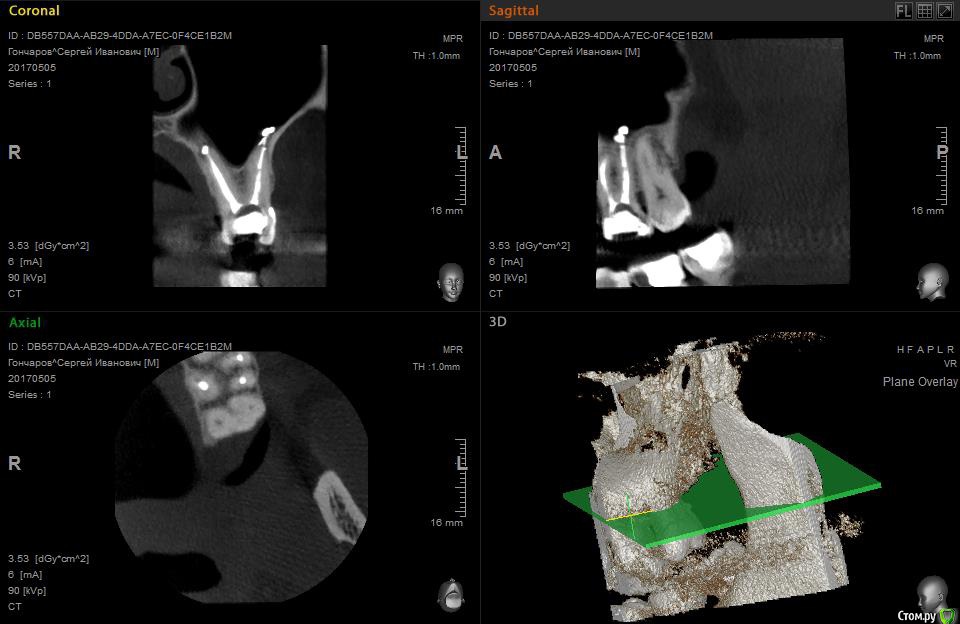

Больше месяца назад вывели эндометазон за верхушку корня на ~ 5 мм, и в

гайморовую пазуху ~5 мм. Один стоматолог сказал, что ничего делать не надо, заживать будет долго, другой направил в лор хирургию на гайморотомию , но там отказались без

наличия гайморита. Общее состояние ухудшается, слабость, похоже на аллергическую реакцию, появились и усиливаются боли в сердце.